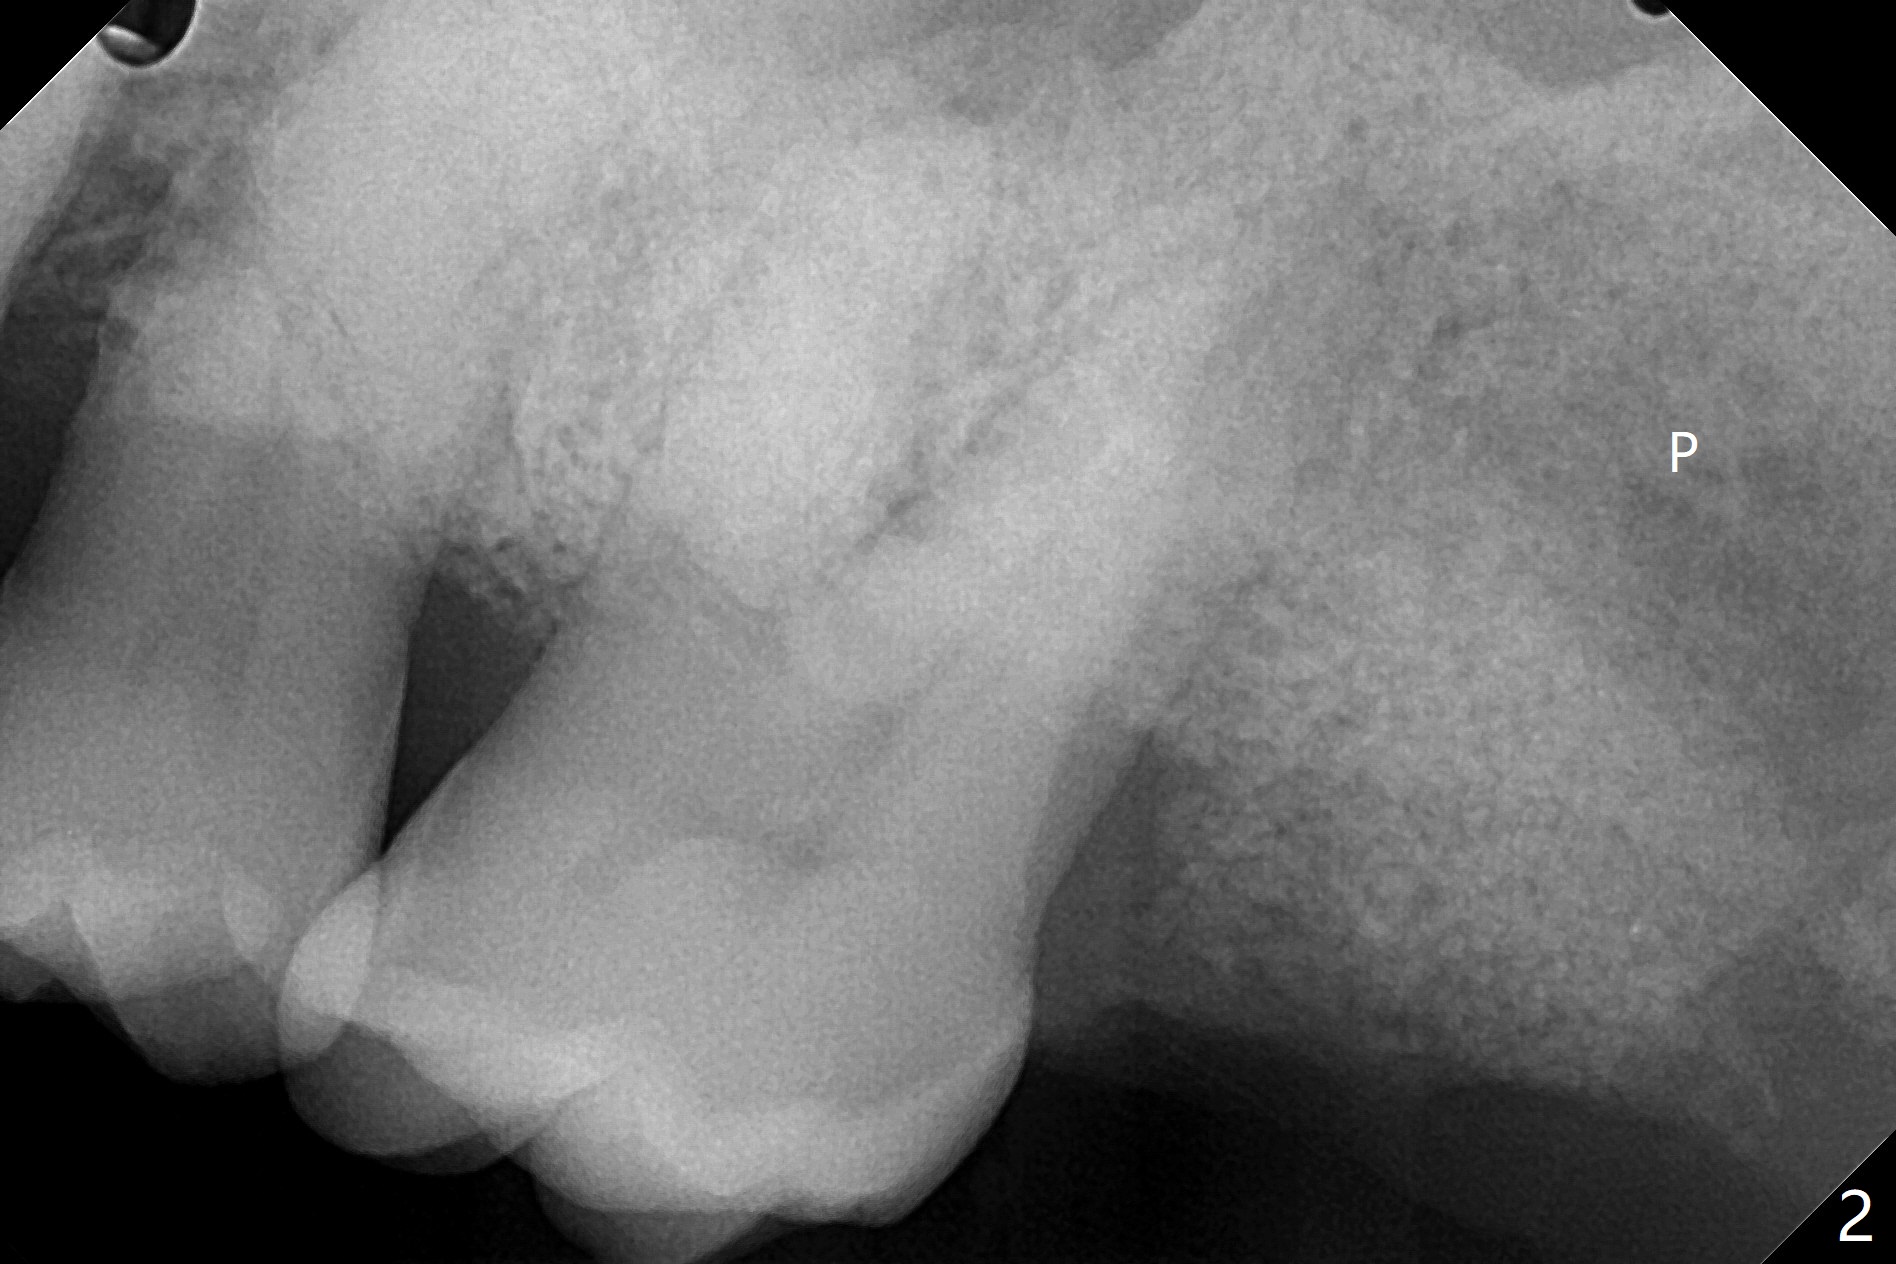

53岁黑男要求拔除松动,剧烈疼痛的左上7(图一(*:上颌窦底板)),同意植骨,分期付款。拔牙后牙槽窝硕大,有许多难以刮除的肉芽组织,出血多,颊侧骨壁应该缺失。在放置GEM21S人工合成骨和异体骨(主要部分)前,在牙槽窝深部放置两个Osteogen塞(图二:P,止血,所谓胶原骨,另外一种人工合成骨),覆盖不可吸收膜,PTFE缝线,间隙保持器,牙周敷料。由于对合牙是智齿,垂直高度有限,放置保持器和敷料有困难。去除炎性肉芽组织,使用两个大小不太带齿刮匙,血管钳,特殊镊子以及带金刚石镊子(图三),反复多次使用自配生理盐水(图四)冲洗。